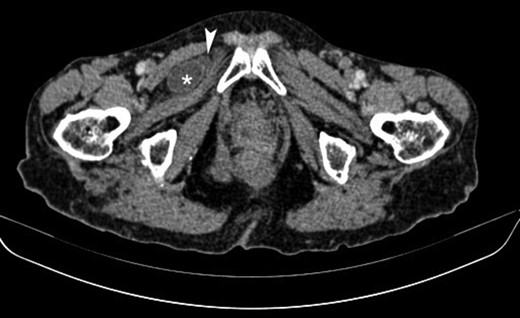

Axial contrast-enhanced CT image showing a small bowel loop (asterisk) appearing herniated and situated superficially to the obturator externus muscle and deep to the pectineus muscle on the right. Note is made of a small fluid collection adjacent to the herniated loop (arrowhead).

The patient, was admitted to the hospital’s emergency department with a 24-h evolution of diffuse abdominal pain and progressive abdominal distension, associated with persistent vomiting and irradiating pain to the right leg. Patient had a previous history of abdominal surgery including laparoscopic cholecystectomy and repair of umbilical hernia, as well. Physical examination revealed an under-weight female, with distended and tympanitic abdomen, hyperactive bowel sounds with audible rushes associated with vigorous peristalsis, diffuse abdominal pain to deep palpation and no signs of peritoneal irritation or inguino-abdominal hernias. There were neither faeces nor intraluminal mass or blood on the digital rectal examination. Besides, Howship–Romberg sign was negative. The patient maintained her haemodynamic and ventilatory stability. Naso-gastric tube drained ~300 mL of fecaloid fluid. Laboratory exams showed leukocytosis (14 280–70.01% neutrophils) and an increased C-reactive protein level (4.3 mg/L). Upright radiographs demonstrate multiple, short air-fluids levels. Based on the suspicion of an acute bowel obstruction a CT of the abdomen and pelvis was the best applicable solution. The CT scan identified a small intestine segment strangulated through the right obturator foramen and an intestinal distension proximally (Fig. 1). Soon after, the patient underwent an emergent infraumbilical midline laparotomy that confirmed the diagnosis; right obturator hernia with ileal partial wall strangulation (Richter’s type). This was gently released and found to be congested although still viable. Once the bowel loop was released and subjected to warm packs, the colour returned to normal. The obturator hernia defect was roughly 1 × 1 cm2 and this was closed using a single stitch of absorbable polyglactin no. 2 suture (Fig. 2). No other pathology was found. Mass closure of laparotomy wound was with loop polydioxanone (PDS) suture and clips to close the skin. The patient remained stable postoperatively over the course of her hospitalization. She tolerated an oral diet on the second and was discharged on the fourth postoperative day respectively, with an uneventful postoperative recovery.